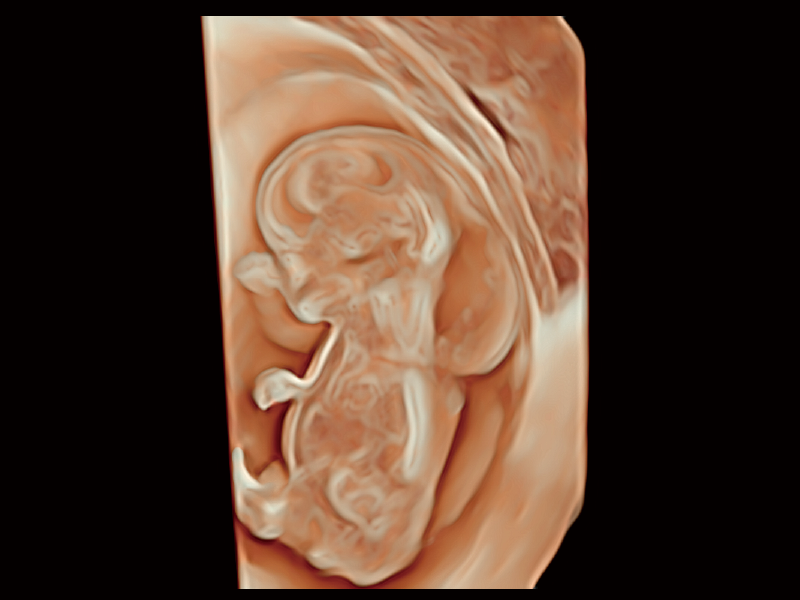

作為開(kāi)立醫(yī)療全新打造的超高端旗艦超聲產(chǎn)品,從探頭抬起喚醒開(kāi)啟掃查到多維探頭發(fā)射接收,通過(guò)先進(jìn)的場(chǎng)成像發(fā)射、自適應(yīng)聚合重建等技術(shù),基于RF Data原始射頻數(shù)據(jù)在圖像生成、高端功能等方面實(shí)現(xiàn)突破,為婦產(chǎn)科、兒科提供全方位臨床解決方案。

夢(mèng)溪?P80以“關(guān)愛(ài)女性”為基石,提供全方位的解決方案,量身定制以滿(mǎn)足女性的健康需求,涵蓋婦科、生殖健康檢查、產(chǎn)前篩查及產(chǎn)后康復(fù)等領(lǐng)域。